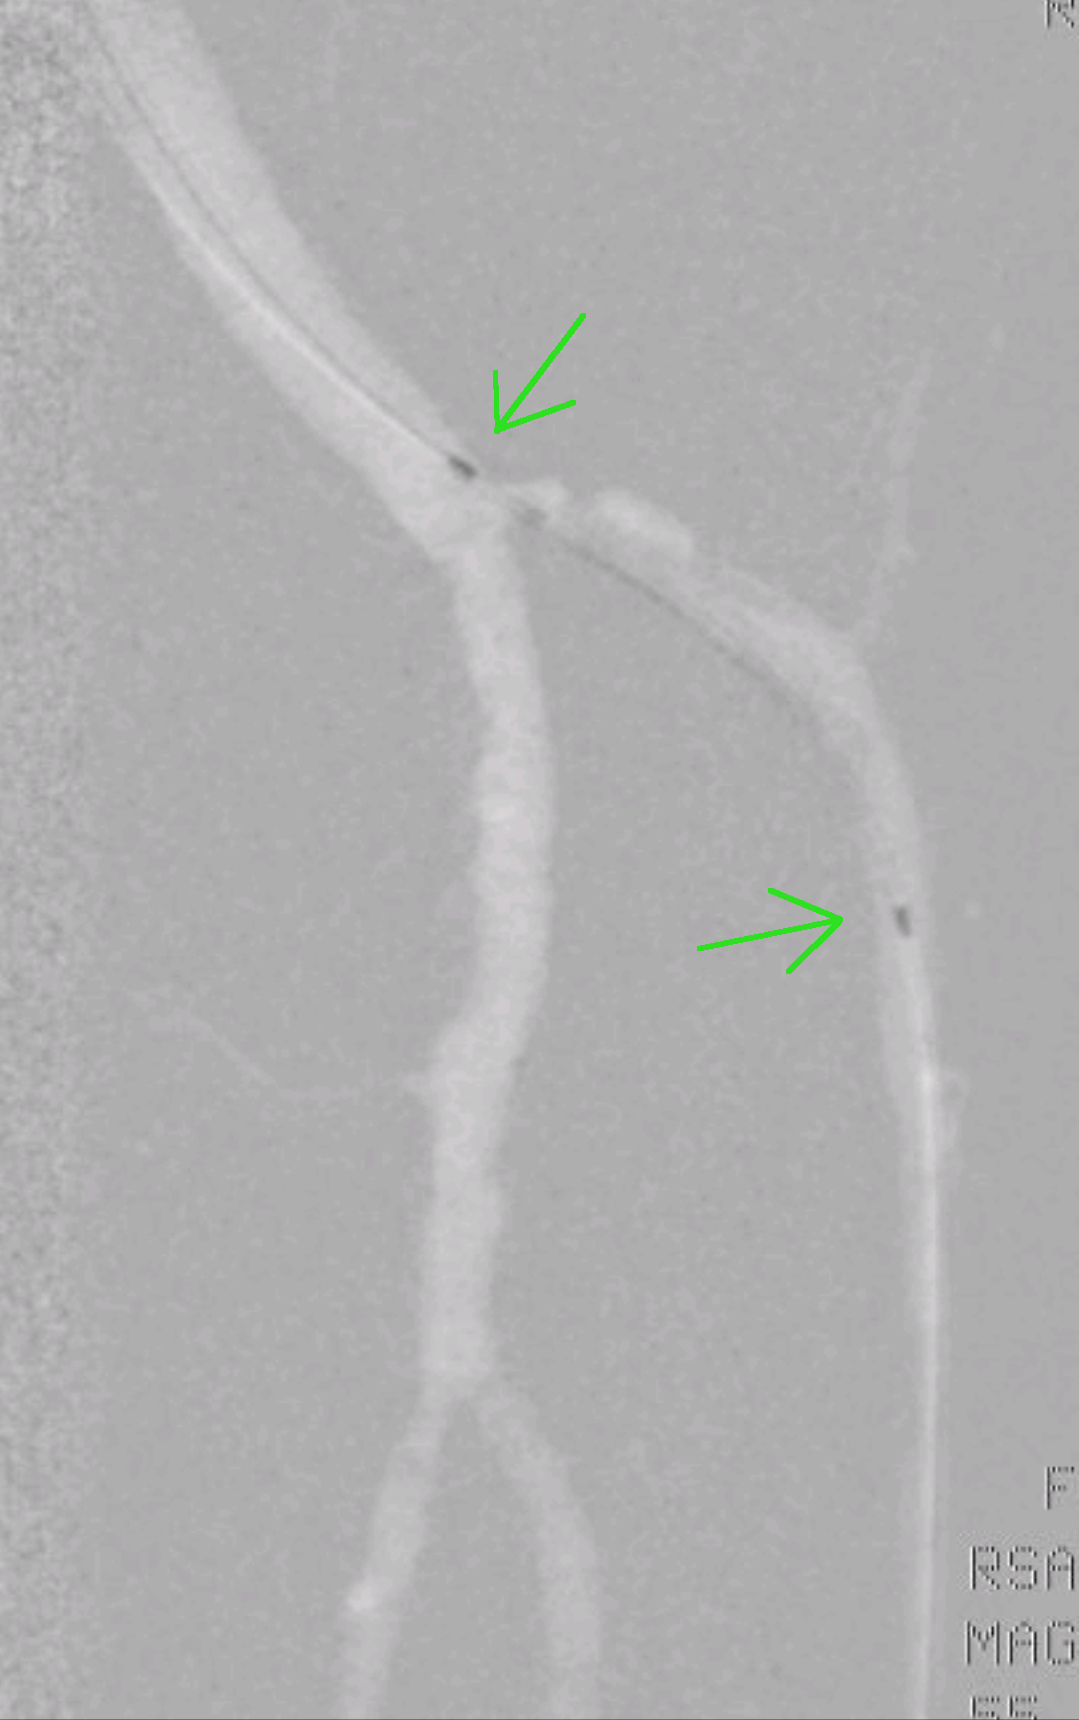

Pozicioniranje žilnega balona (zeleni puščici). Žilni balon se bo napihnil med obema temnejšima markerjema. Z napihnjenjem bo balon razširil žilo. Ponovno se bo po žili vzpostavil dober pretok krvi.